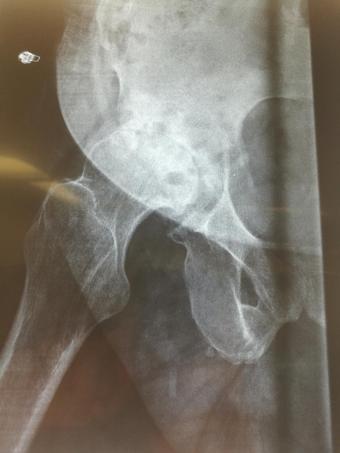

Компанія Lima надала стажування в ортопедичній приватній клініці місті Афіни Греція в листопаді 2019 року. Ендопротезування кульшового суглоба протезами компанії Lima малоінвазивним передньо-латеральний доступом у професора Христодулоса.